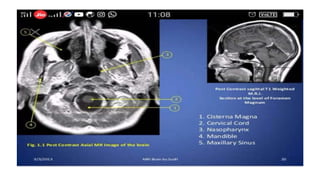

Sagittal T1 (Normal)

Chiari Malformation (Sagittal T1)

Chiari Malformation (Axial T1)

Normal T1 Contrast

T1 • Provides themost anatomically-relevant images • Fluid (in CSF and orbits) is dark • Grey matter is darker than the white matter